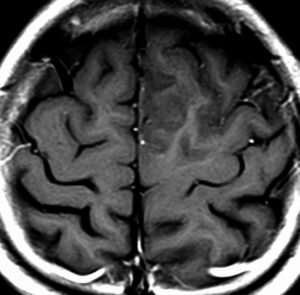

diffuse, infiltrative びまん性のもの

染み込むように左前頭側頭葉から島回に広がるAAです。T2/フレア像でにじむように広がり,ガドリニウム増強されません。グレード 2 (びまん性星細胞腫)と区別が難しいものです。

もちろん手術摘出できないもので,生検手術のみを行います。この大きさのものに60グレイの放射線治療をすれば高度の認知機能低下は避けられませんから,患者さんと照射線量をよくよく相談します。でもAAは放射線化学療法で長期生存が望めます。50-54グレイの線量が選択されます。